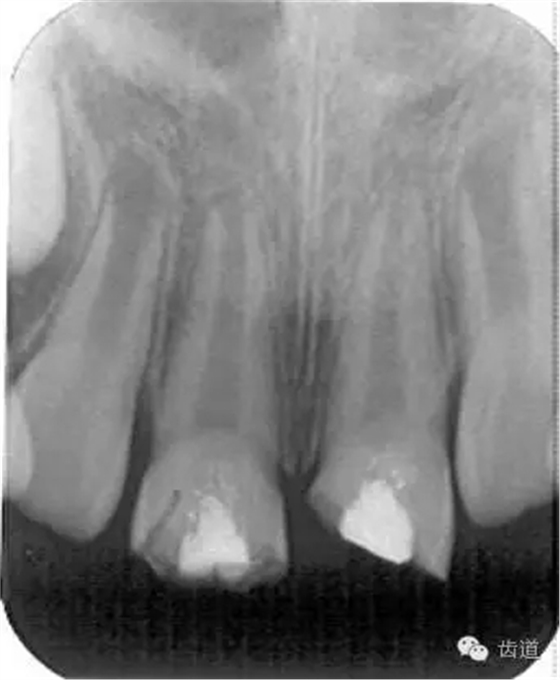

術(shù)后一個(gè)月

術(shù)后當(dāng)天

術(shù)后11個(gè)月

術(shù)后五個(gè)月